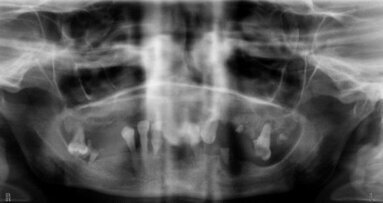

W badaniu przedmiotowym zewnątrzustnym nie stwierdzono zmian patologicznych. Wewnątrzustnie: braki zębów 26, 37, 35, 45, oraz brak zęba 14 uzupełniony koroną protetyczną wspartą na wszczepie. Szerokość części zębodołowej żuchwy w miejscu braku zęba 35 nie przekracza 5 mm, w miejscu braku zęba 37 – 6 mm. Na zdjęciu pantomograficznym zęby 16, 36 i 46 leczone endodontycznie. W okolicy wierzchołka korzenia zęba 46 ograniczone rozrzedzenie struktury kostnej mogące odpowiadać ziarniniakowi okołowierzchołkowemu. W miejscu planowanej implantacji, okolicy braku zębów 35, 37 prawidłowa struktura tkanki kostnej. Odległość od krawędzi części zębodołowej żuchwy do sklepienia kanału żuchwy w miejscu braku zęba 35 – 18,5 mm, 37 – 18 mm.

Na podstawie wyniku badania klinicznego i po analizie zdjęć radiologicznych zaproponowano pacjentowi kolejny etap leczenia implantoprotetycznego obejmującego wprowadzenie 2 implantów śródkostnych XiVE (Dentsply) w miejsce braku zębów 35 (implant Ø 3.0 dł. 13 mm) oraz 37 (implant Ø 3.4 dł. 11 mm).

Wykorzystując zestaw naprawczy, z powodzeniem udało się odzyskać złamany fragment (Ryc. 5). Wnętrze implantu obficie przepłukano roztworem soli fizjologicznej i zamknięto śrubą do czasu ostatecznej osteointegracji. Zalecono wykonanie kontrolnego zdjęcia pantomograficznego (Ryc. 6). Przebieg pozabiegowy bez powikłań. Po 3 miesiącach pacjent zgłosił się w celu odsłonięcia i zaopatrzenia śrubami gojącymi wszczepionych implantów (Ryc. 7). Leczenie zostało zakończone wykonaniem i osadzeniem uzupełnień stałych w postaci koron metalowych licowanych porcelaną – przykręcanej w miejscu brakującego zęba 37 oraz cementowanej w miejscu 35 (Ryc. 8 i 9).